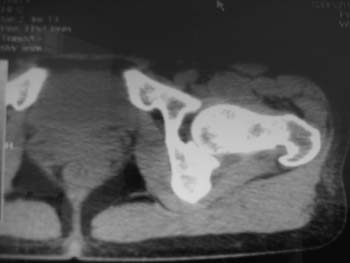

以下是引用358450m在2008-8-12 12:12:00的发言:[br]骨囊肿

以下是引用yangyudong333在2008-8-12 14:30:00的发言:[br]考虑退京变所致关节面下骨质囊变

以下是引用随光逐影在2008-8-12 20:40:00的发言:[br]考虑邻关节骨囊肿或骨内腱鞘囊肿。